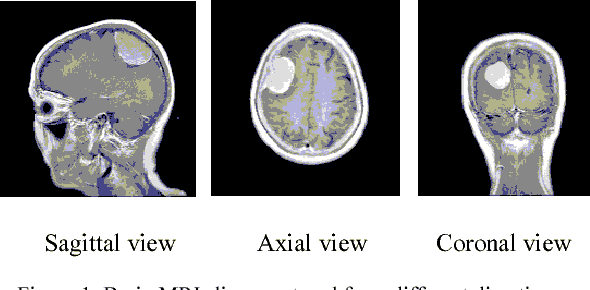

Abstract:Recently deep learning has been playing a major role in the field of computer vision. One of its applications is the reduction of human judgment in the diagnosis of diseases. Especially, brain tumor diagnosis requires high accuracy, where minute errors in judgment may lead to disaster. For this reason, brain tumor segmentation is an important challenge for medical purposes. Currently several methods exist for tumor segmentation but they all lack high accuracy. Here we present a solution for brain tumor segmenting by using deep learning. In this work, we studied different angles of brain MR images and applied different networks for segmentation. The effect of using separate networks for segmentation of MR images is evaluated by comparing the results with a single network. Experimental evaluations of the networks show that Dice score of 0.73 is achieved for a single network and 0.79 in obtained for multiple networks.